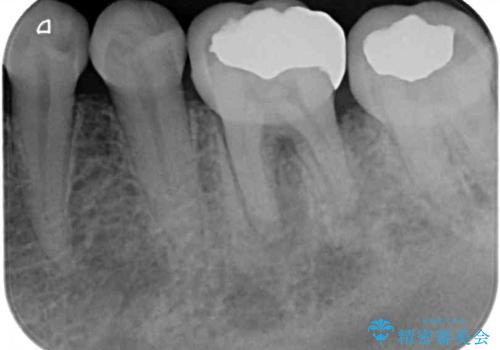

以前むし歯治療をした後から定期的に痛むことがあるとのことで、レントゲン写真より神経組織が失活していることが予想されました。

銀歯を外すと神経組織の一部が取り除かれており、歯根に付け根に穴が空けられている状態でした。

出血の原因は以前の治療で空けられた穴であると考え、封鎖をするとともに根管治療を行い、その後オールセラミッククラウンにて補綴治療を行うこととしました。